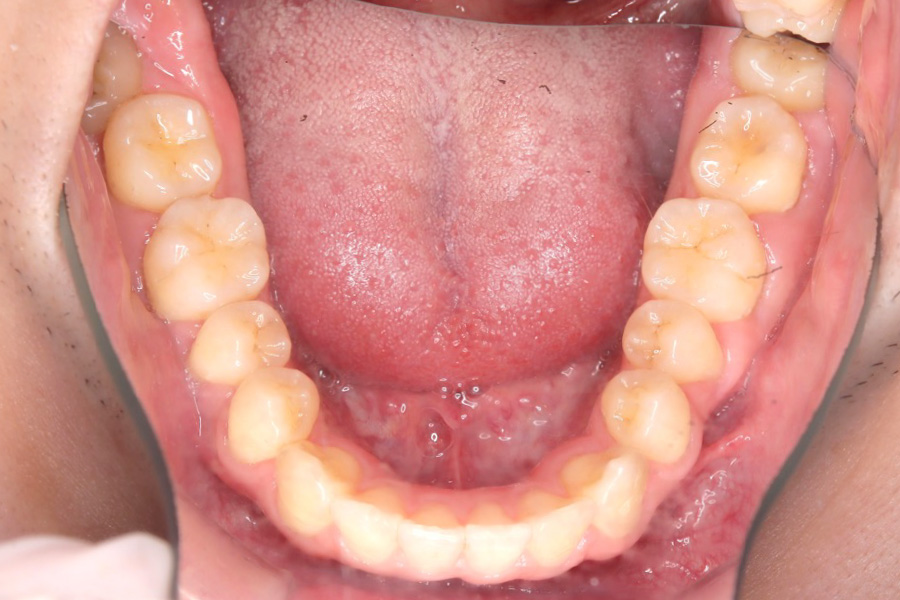

治療前

主訴 歯のガタつき

治療内容 インビザライン矯正

非抜歯